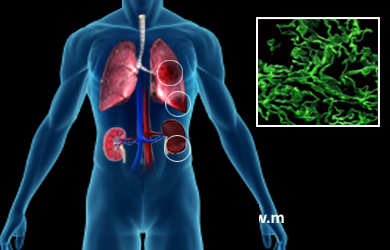

Что такое синдром ГудпасчераСиндром Гудпасчера – тяжелая патология, представляющая собой аутоиммунный синдром с легочным кровотечением и гломерулонефритом. Это системный капиллярит с преимущественным поражением легких и почек по типу геморрагических пневмонита и гломерулонефрита. Заболевают чаще мужчины в возрасте 20 - З0 лет. Согласно медицинским наблюдениям, синдром Гудпасчера чаще всего развивается у людей, имеющих наследственную предрасположенность, которые курят сигареты. Дополнительными отрицательными факторами являются вирусные инфекции, вдыхание углеводородов и некоторые другие факторы. Отмечается связь с вирусной и бактериальной инфекцией, переохлаждением.

Каков же патогенез синдрома Гудпасчера? Под воздействием одного из вышеперечисленного фактора в организме начинаются вырабатыватся аутоантитела к компонентам мембран легочных альвеол и почечных клубочков. Возможно, в роли антигена к вырабатываемым антителам выступает один из компонентов цепи коллагена 4 типа, который присутствует как в альвеолах, так и почечных капиллярах. Антитела взаимодействуют с антигеном, образуя иммунные комплексы, что приводит к индукции воспалительного процесса и поражения почечных клубочков и альвеол.

Из специфических симптомов синдрома Гудпасчера, как правило, первыми поражаются легкие; у больного отмечается кашель, прогрессирующая одышка, боли в грудной клетке, кровохарканье и легочное кровотечение. Нередко при синдроме Гудпасчера отмечается осложнение в виде сердечной астмы и отека легких.

К легочным проявления синдрома через определенное время присоединяются и почечные симптомы: олигурия, гематурия, артериальная гипертензия, периферический отек и другие. В ряде случаев синдром Гудпасчера сопровождается артралгией, миалгией, кожными геморрагиями, перикардитом и некоторыми другими симптомами.